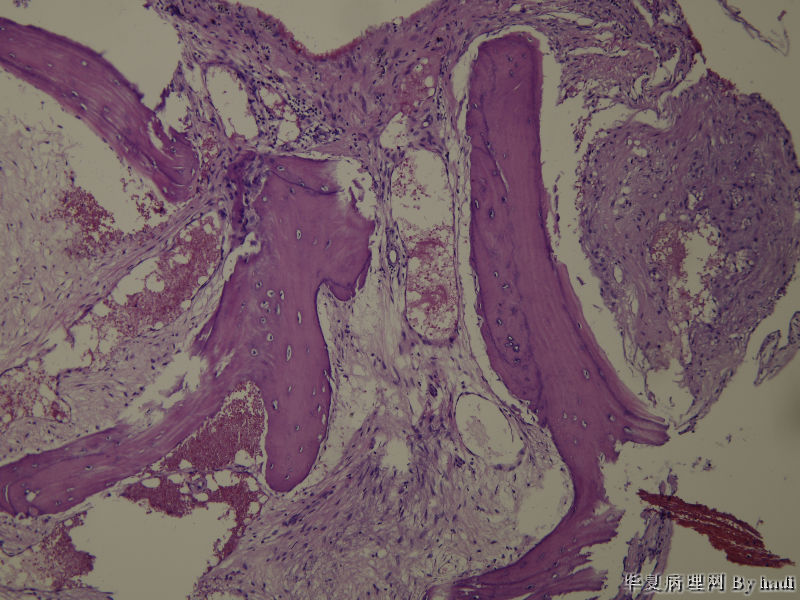

• 鼻腔肿瘤图2

图2